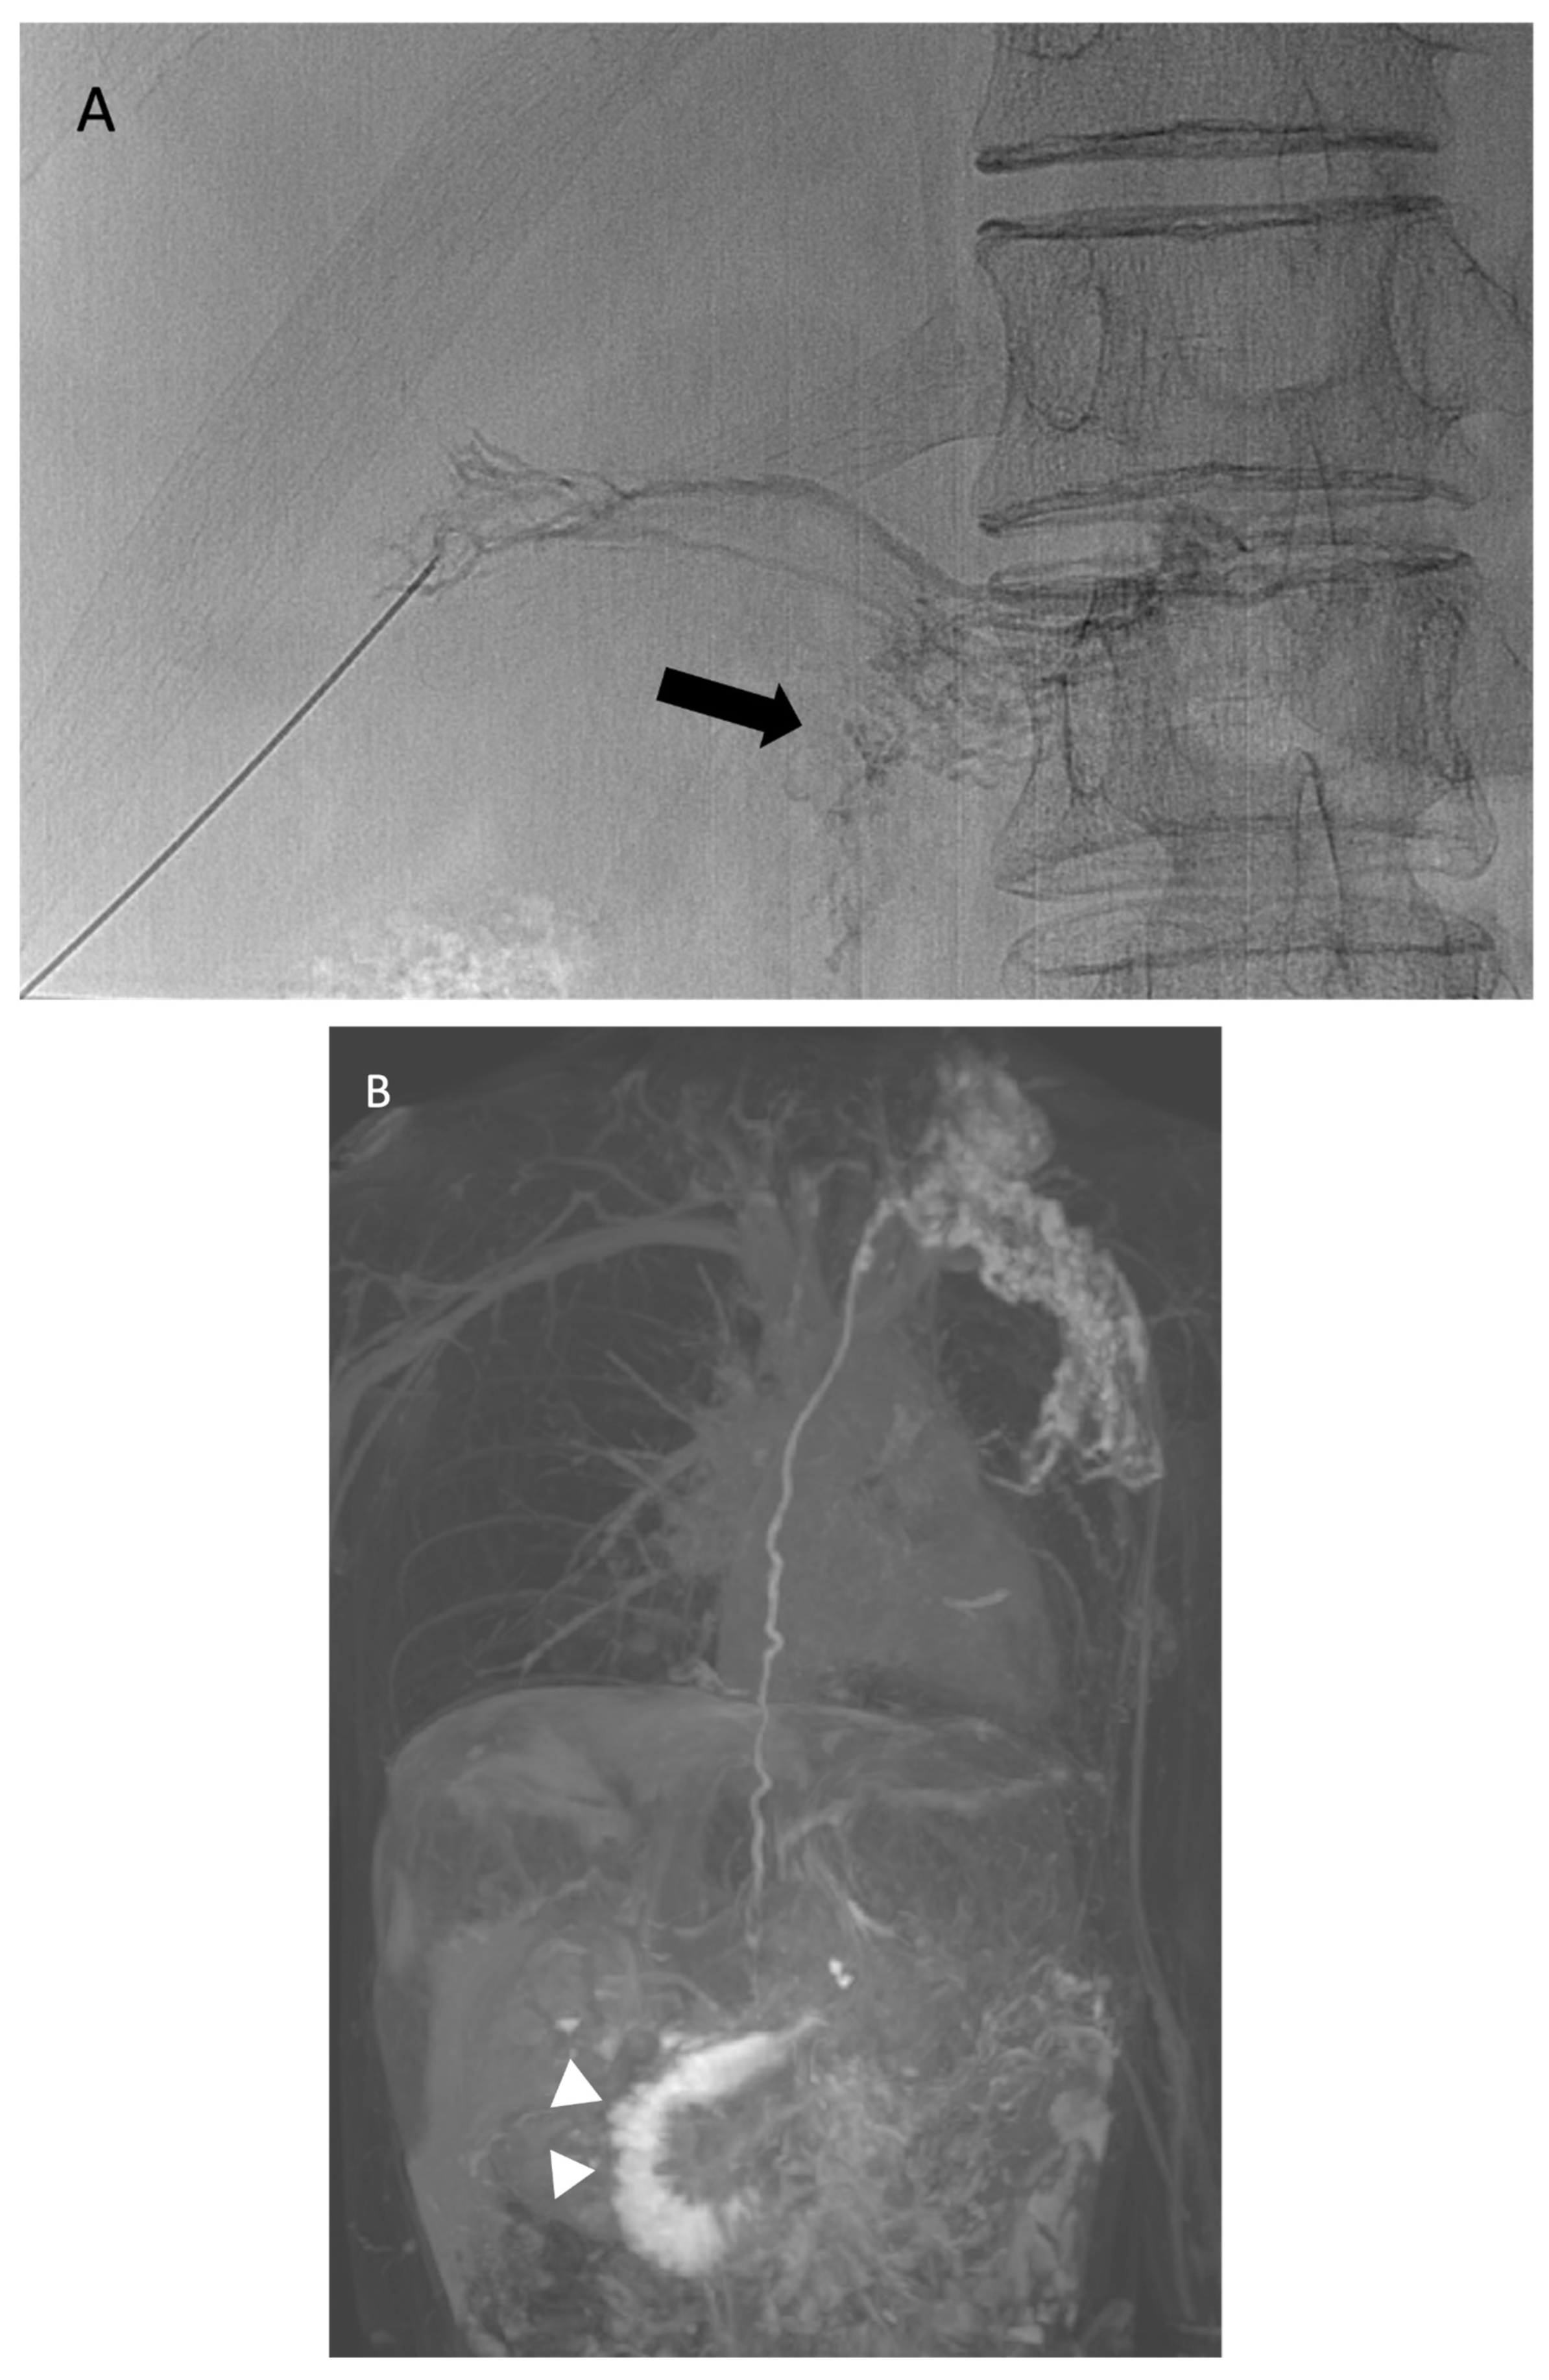

Figure 9. Thoracic duct embolization in a 50-year-old woman with plastic bronchitis of unknown etiology. (a) Clinical photograph of a lymphatic non-inflammatory cast produced by the patient. The branching pattern indicates it originated from the airways and took the shape of the hollow structures from where it was formed. The patient indicated that she could sense the obstruction on the right side. (b) Thoracic duct lymphangiography executed in a similar fashion as the patient in Figure 7. Black arrows indicate a large abnormal collateral vessel tracking to the right mainstem bronchus and upper lobe airways. The topmost arrow indicates a pooling of contrast consistent with a leak. The black bracket indicates otherwise normal thoracic duct anatomy. This thoracic duct was embolized in the same fashion as the patient in Figure 7.